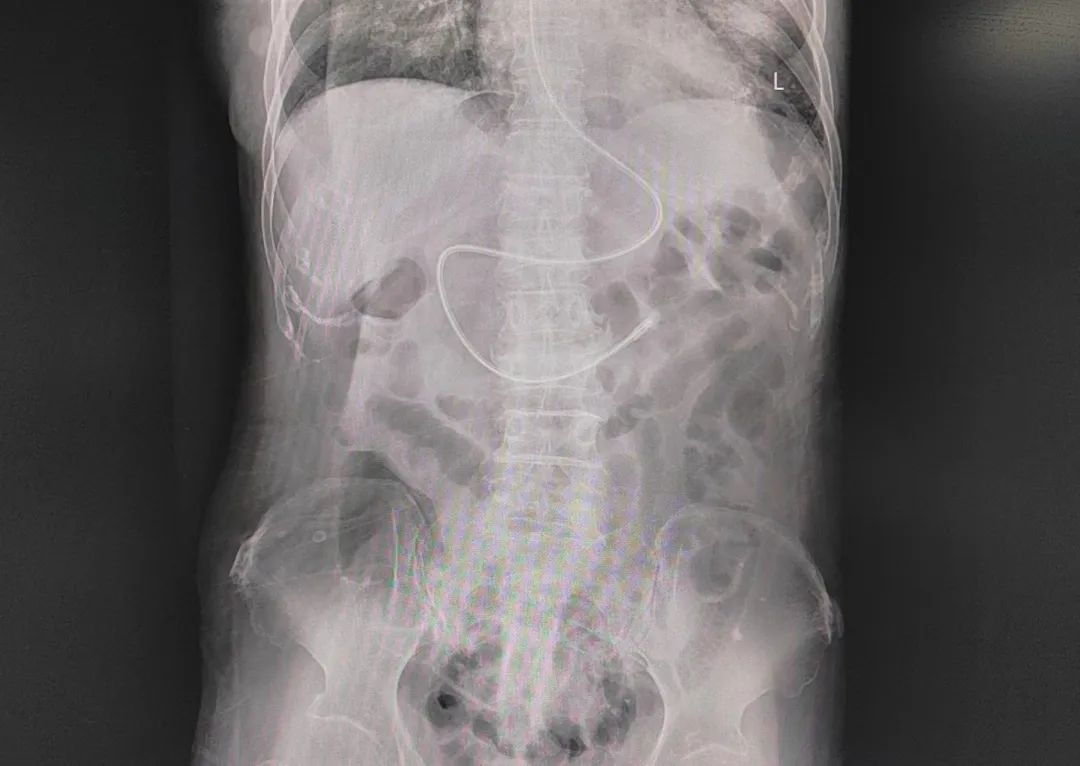

需给予肠内营养的患者传统经鼻胃管喂养容易引起返流、误吸、食管气管瘘等风险;而经鼻空肠营养管肠内营养可有效预防返流、误吸发生,降低肺部感染发生率,并可保证营养供给,是肠内营养的重要支持方式。我科护士白建芳利用所学技术在科内逐渐开展盲插空肠管技术,目前,已成功置管4例,进一步提升了我科危重病人救治能力和危重患者的专业护理水平。